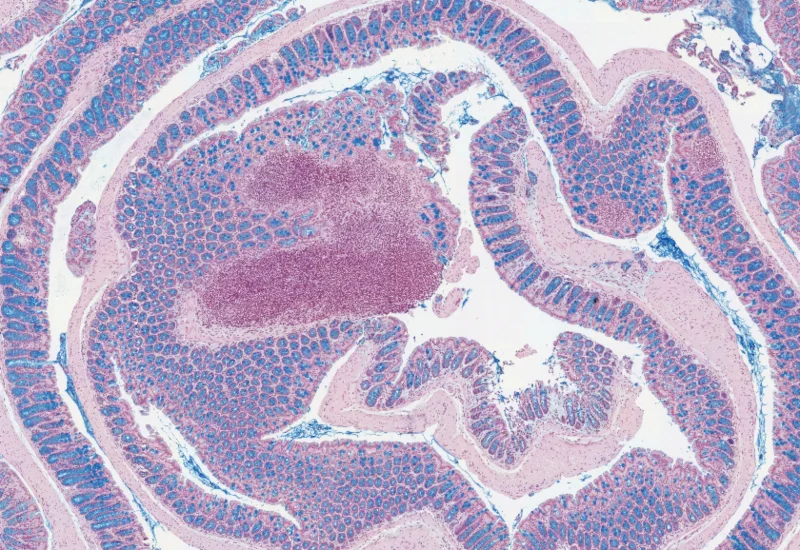

Mucin Swiss Roll

The Mucin Swiss Roll App segments tissue into subclasses, detects nuclei and mucin (e.g. PAS-stained), and outputs tissue areas, cell counts, and mucin area per region and overall.

mouse, colon, mucin, immune cell follicles

The Mucin Swiss Roll App allows for detection of the swiss roll, and the segmentation into different subclasses (mucosa, immune cell follicles, connective tissue, background). Further it detects nuclei and (e.g. PAS stained) mucin. The App outputs area (µm2) of detected tissues/tissue classes, count of total cells and in each detected area as well as the area of stained mucin in the entire tissue and within the subclasses.